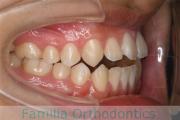

No.23V-069

- 主な症状:

- 上下顎前突

- その他の症状:

- 叢生

- 年齢:

- 25歳

- 性別:

- 女性

- 抜歯部位

- 上:

- 44

- 下:

- 主な使用装置:

- FEA 022

- 治療にかかった費用:

- 88万円

前歯のでこぼこと口元の突出感を治したいということで来院されました。上下の前歯の突出がある上下顎前突と叢生のケースでした。上下左右から小臼歯を抜歯を抜歯してマルチブラケット法にて治療を行いました。2年強、25回程度の通院が必要でした。

特に治療前に内側に入っていた上の側切歯の後戻りリスクが大きいケースです。